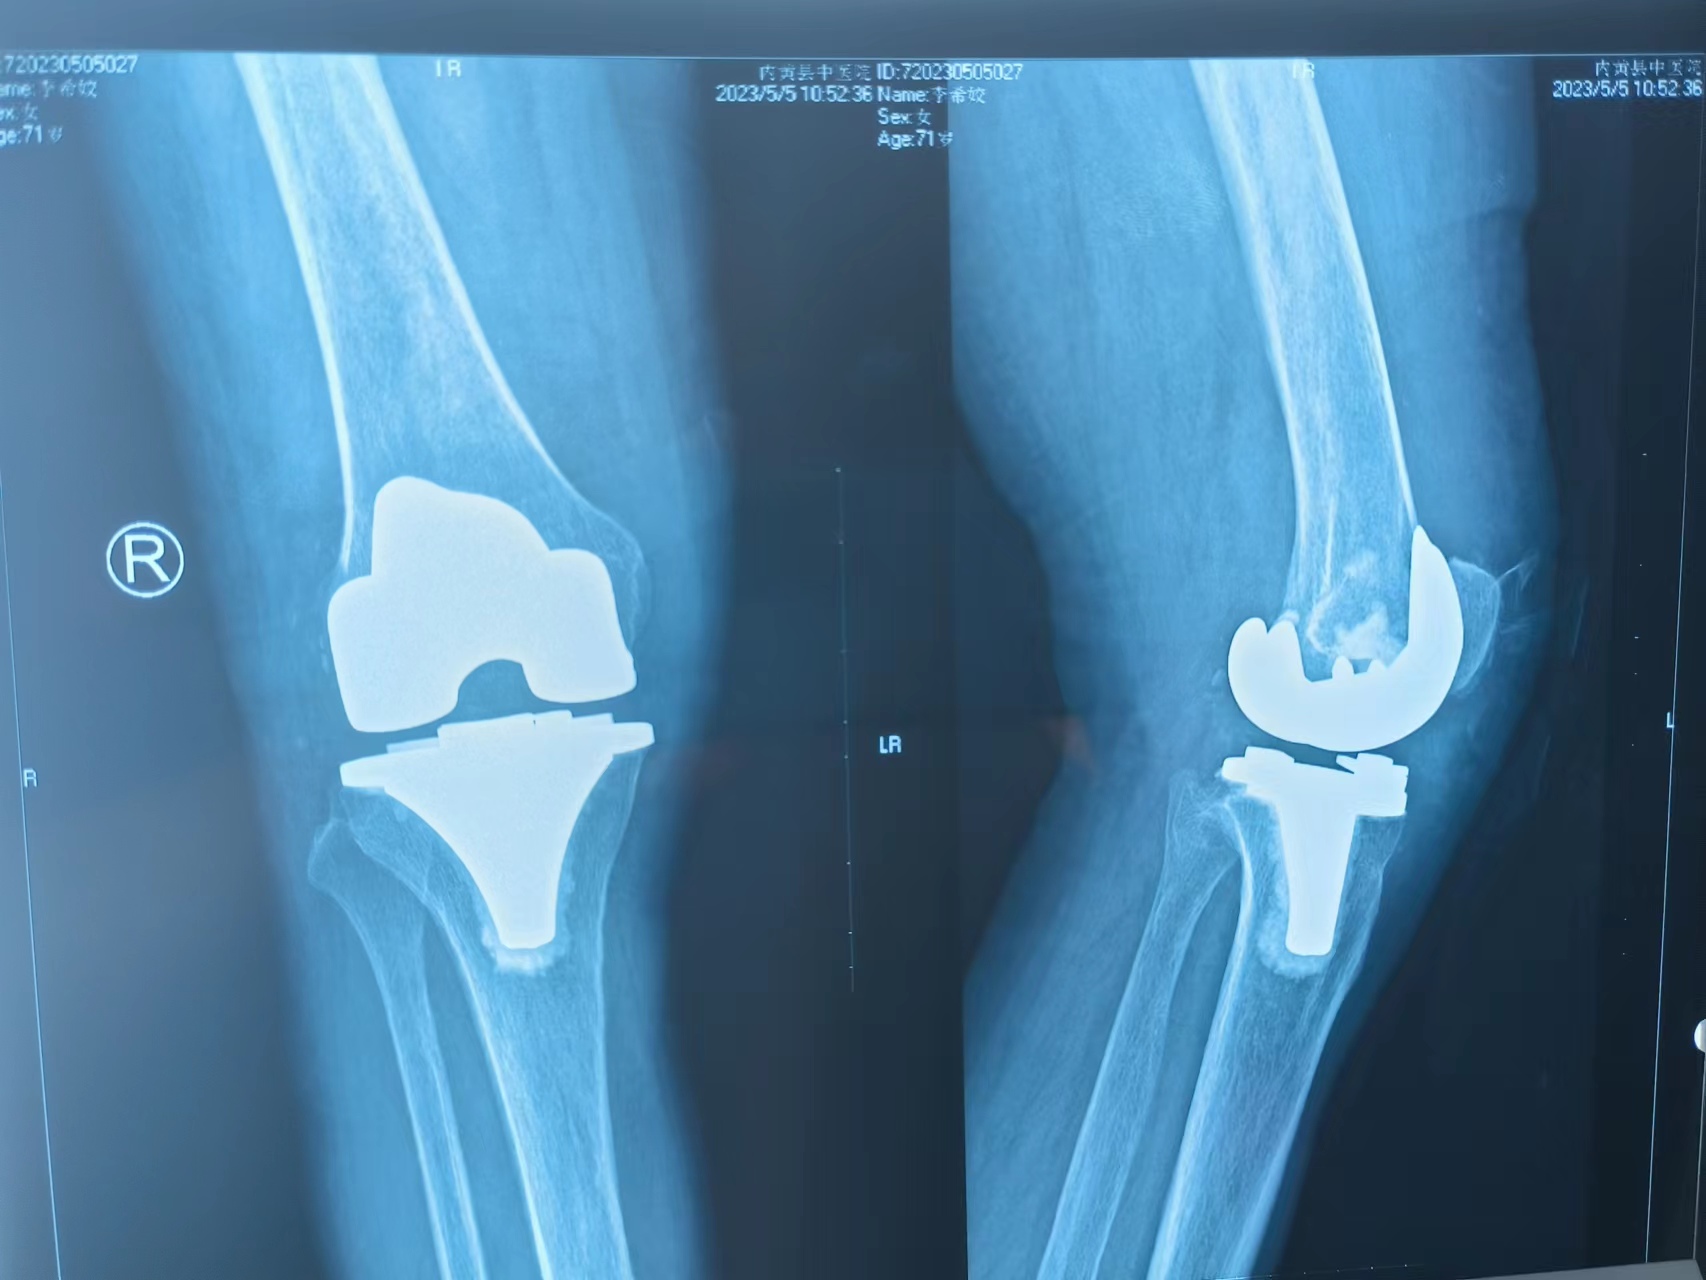

C、关节假体不同:

2、全膝置换:全膝置换是针对整个膝关节进行置换,包括胫骨平台、股骨远端部位等,所以假体相对较大,患者术后关节活动的自如度略小。